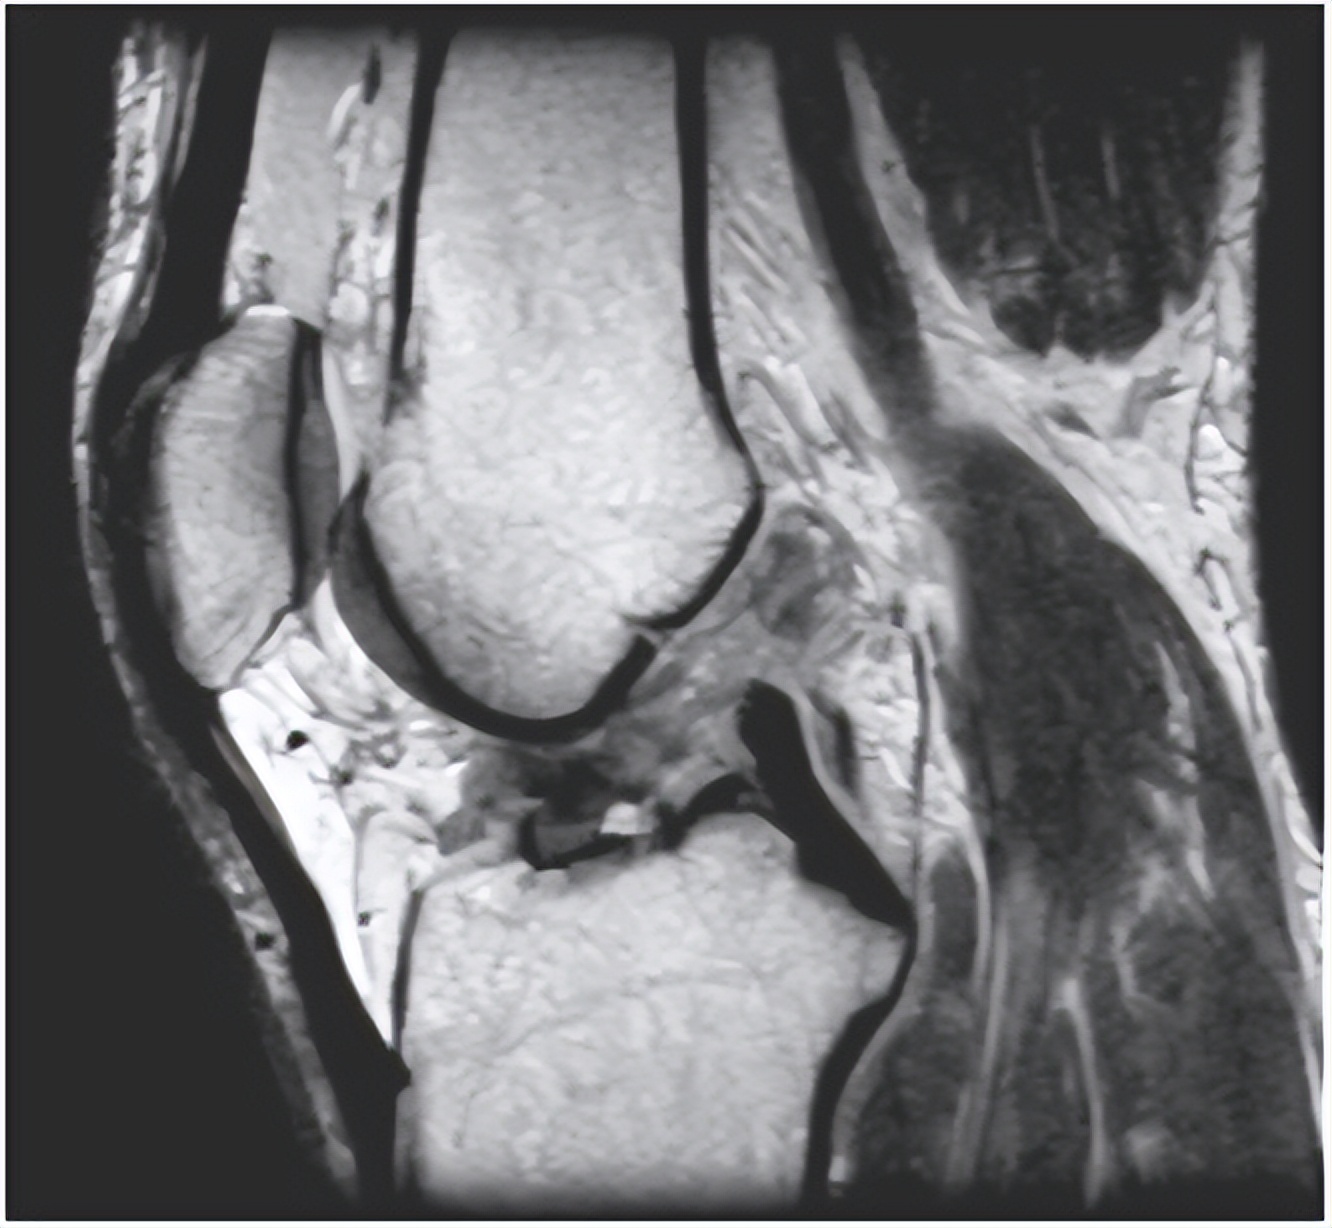

临床上有这样一个案例,是我之前看的一个患者,他因膝关节外伤,导致膝关节肿胀、行走不便,后到医院检查,核磁共振报告上显示有少量积液。随后我帮他做了体格检查,前抽屉试验呈阳性,Lachman试验,看见胫骨明显向前移位,也呈阳性,再看MRI发现他的前交叉韧带已完全断裂。后来我帮他做了膝关节镜下前交叉韧带重建手术。三个月后,患者基本上恢复了正常。

我讲这个案例的意思是想告诉大家,膝关节积液,并不一定仅仅是膝关节积液,有可能是膝关节其他部位的损伤或者其他的疾病导致。关节积液只是一种临床表现,更加具体的原因因人而异。有的人可能伴随关节内半月板、韧带、软骨等问题的出现,我们要明确一点,核磁共振的报告仅作参考,具体还需要根据患者的病史、体格检查,并结合MRI,必要时还可做关节镜下检查来明确诊断。一定要进行全面的评估检查,再进行针对性的治疗和康复训练。